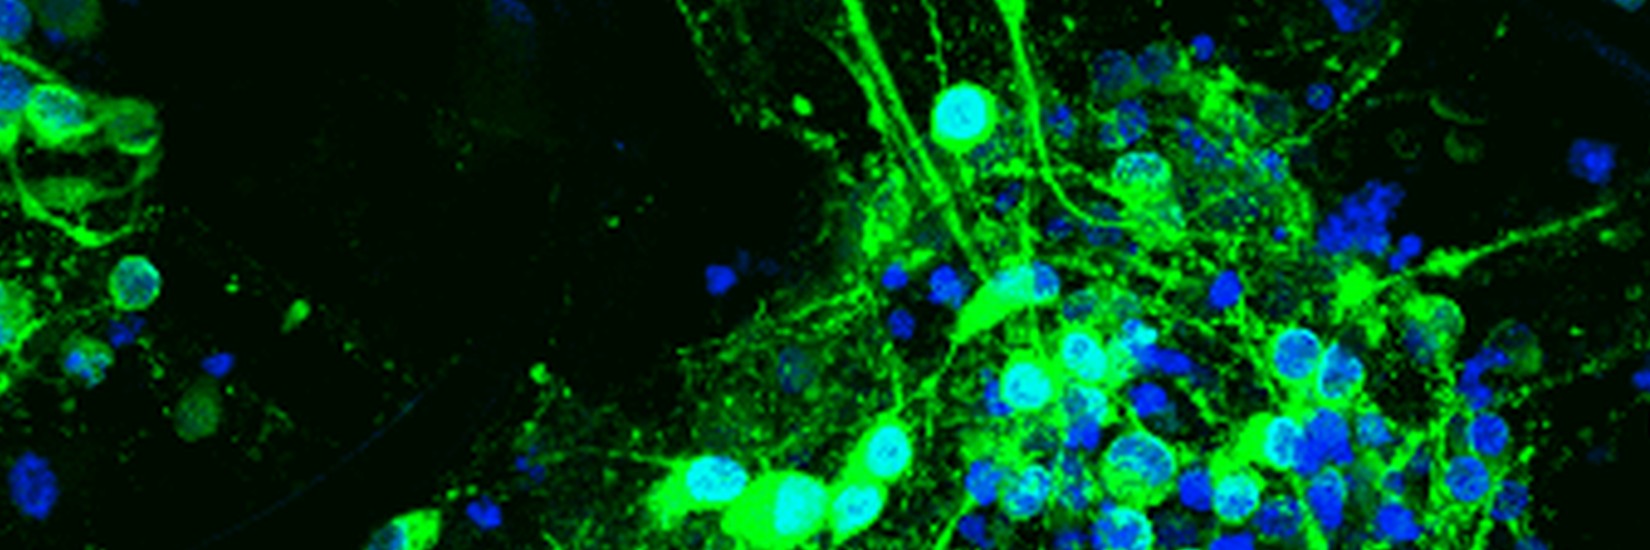

This prestigious European grant is endowed with a total of 2.5 Million € over 5 years and is awarded in fierce competition to excellent researchers for visionary research projects. Prof. Chichkov's interdisciplinary research project deals with a fundamental problem of regerative medicine:

Laser biofabrication of 3D multicellular tissue with perfusible vascular network (Laser-Tissue-Perfuse)

PLATFORMA, so der Name des europäischen Konsortiums, will neuartige 3D Zell-Plattformen für das Screening von Kosmetika, Schadstoffen und neuen Therapeutika entwickeln und herstellen. Dadurch können Untersuchungen direkt an menschlichem Gewebe nachgebildet werden, um in Zukunft Tierversuche in diesen Bereichen überflüssig zu machen.